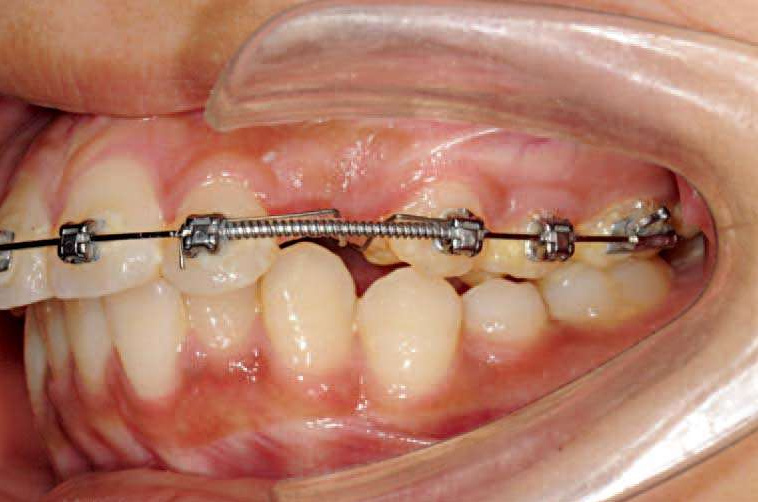

上颌2×4技术,配合口外弓。

①上颌2-2粘托槽,0.012″、0.014″、0.016″、0.018″镍钛,过渡到0.018″不锈钢丝。

②0.018″不锈钢丝在上颌第一磨牙近中做欧米加曲,0.25mm结扎丝向后结扎,配合使用口外弓。

图19 欧米加曲向后结扎